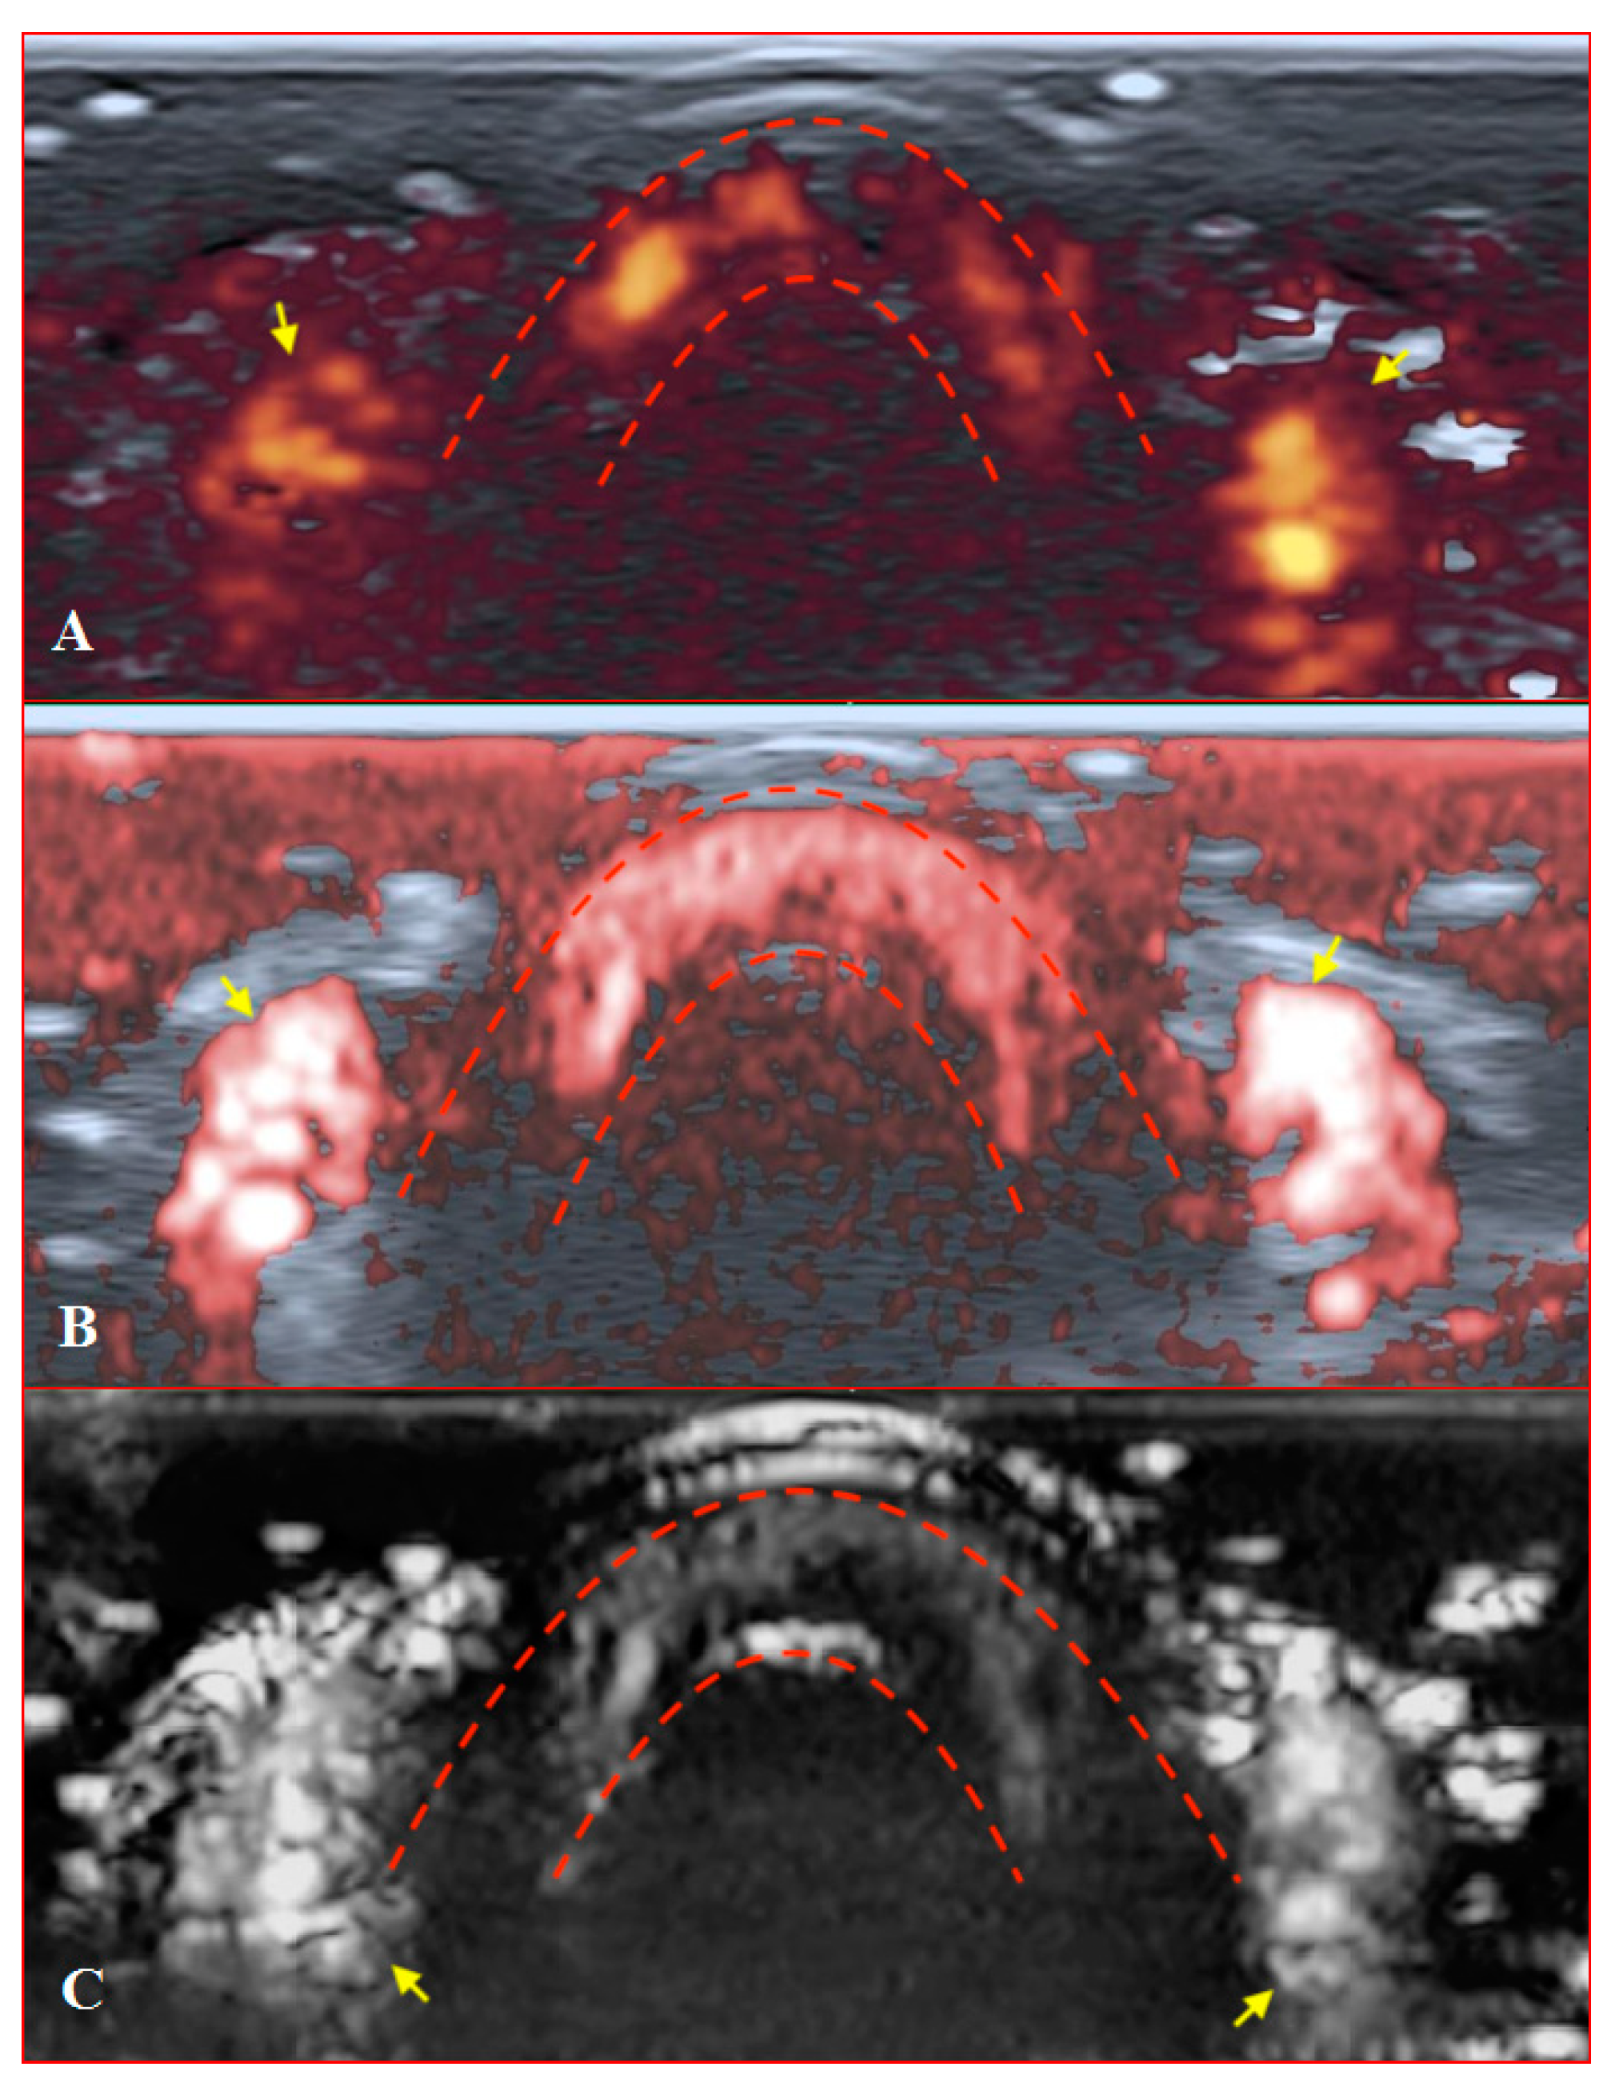

Figure 7. Transverse scans of a healthy fingertip with high gain: (A) PD; (B) cSMI; (C) mSMI. Red dotted lines define the zone between the nail and the surface of a distal phalanx. Yellow arrows mark the lateral nailfold.